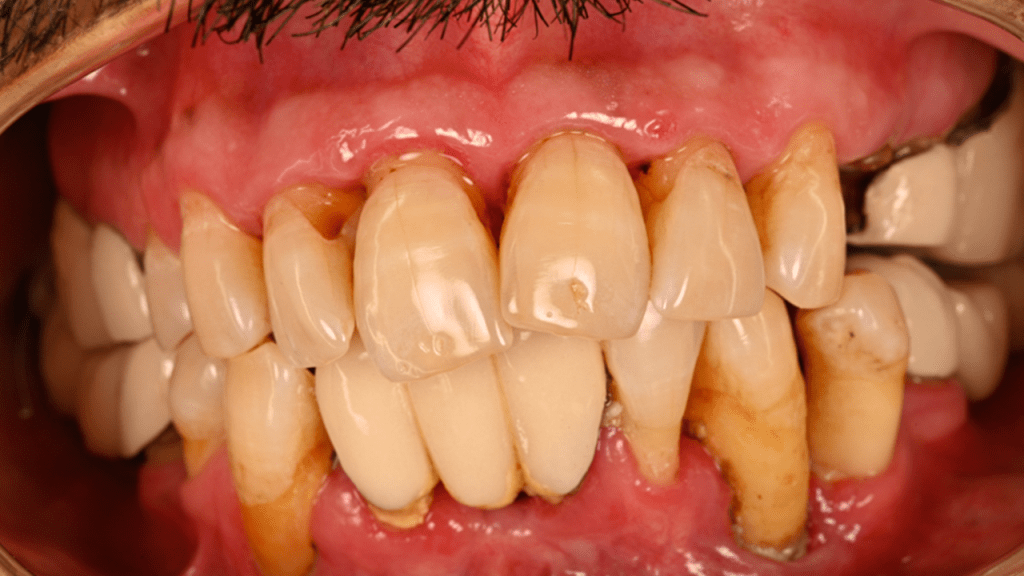

Case is currently in progress: Final tx plan: Crowns #4-11, implants #3, 12×14 fixed bridge, #22 and 27; complete lower overdenture

Patient presented with CC: “My teeth hurt when chewing and I haven’t seen a dentist in over ten years”

3. Allowing tissue to heal after bridge removal, open flap debridement of #4-11, the patient is aware that these teeth may fail and need a full maxillary denture